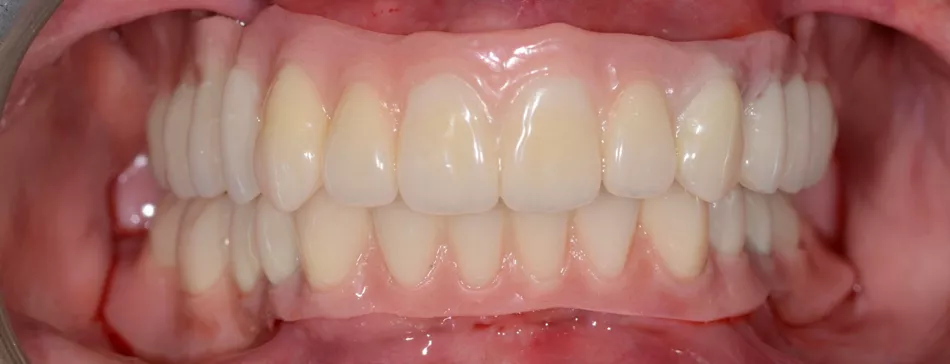

Final rehabilitation of the upper and lower jaws (Figs. 66,67).

The patient’s smile after final prosthetic rehabilitation (Fig. 69).

Fig. 69

The patient’s appearance was noticeably improved, and she was very pleased with the result. She appeared cheerful and satisfied, clearly happy with how everything turned out (Fig. 70).

Fig. 70

The case was planned and carried out using a fully digital workflow, achieving precise implant placement and prosthetic alignment. The Novaloc® system helped reduce invasiveness by allowing implants to be placed in the existing bone while adjusting the prosthetic axes for the removable prosthesis. The patient was very happy with the result, noticing a significant improvement in both appearance and function, and was impressed by how the digital approach enhanced her smile.